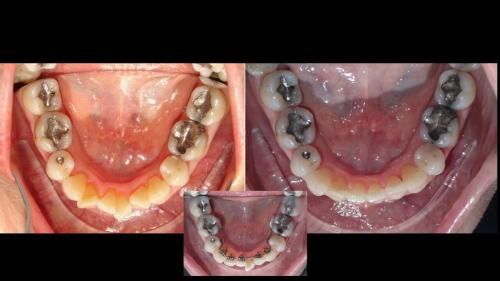

large-Resultados sin que se note ortodoncia

large-Resultados con balance

large-Ortodoncia Lingual

large-Resultado de avance de la mandibula

large-Ortodoncia lingual invisible

large-Lingual

large-Fractura con resina

large-Fractura

large-Combinacion con cirugia

large-Diapositiva14

large-Cambios en el perfil

large-Cambio magico

large-Cambio labial

large-Cambio en el perfil

large-Adultos -Se puede

large-Avance de mordida

large-Sonrisa en adulto

large-Sonrisa Adulto